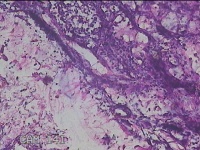

左侧腋下结节

性别

女

年龄

46岁

临床诊断

皮下结节

一般病史

发现左侧腋下一结节1周,伴局部隐痛不适,无发热。

标本名称

大体所见

灰白暗红色组织1.8x1.3x0.3cm一块,表面带梭形皮肤1.8x0.5cm,皮下见结节1.2x0.8cm,切开结节呈实性,切面灰白淡黄色,质软。

炎症性病变。